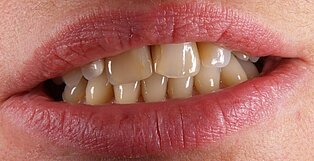

Vom Langzeitprovisorium zur TEK 1 Arbeit